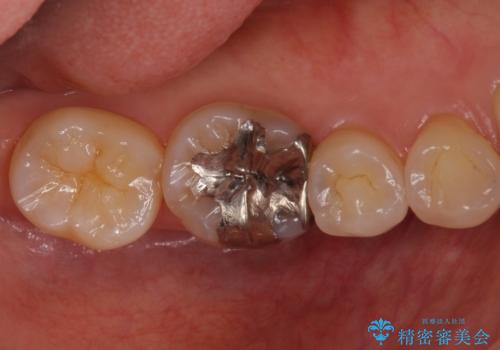

前から2番目の歯が小さく、細くとがった形になっていました。

大きくしようにも、幅が少ない上に、また、内側に入ってしまっているため、矯正治療で前歯を並べてからセラミックでかぶせることにしました。

- 113万円(インビザライン:85万円 前歯セラミック:28万円[ジルコニアクラウンスペシャル 13万円x2本 仮歯1万円x2本])費用は治療当時の料金となります